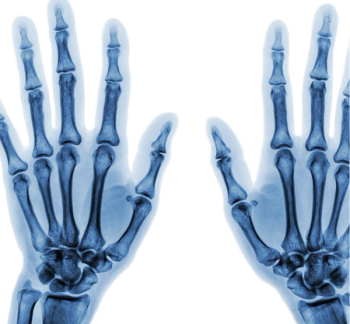

A total of 608 patients from an early RA cohort that had baseline radiographs of hands and feet, as well as at 1, 2, 5, and 8 years, were included in the long-term study.